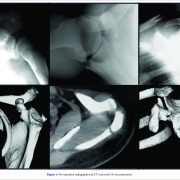

A Comprehensive Review of Triple Disruptions of the Superior Shoulder Suspensory Complex and Case Report

/0 Comments/in Vol 1| Issue 1| Oct-Dec 2016 /by ASESADMIN2016Acta of Shoulder and Elbow Surgery | Volume 1 | Issue 1 | Oct-Dec 2016 | Page 56-61 | Mário Henrique Lobão Gonçalves, Jose Carlos Garcia Jr Authors: Mário Henrique Lobão Gonçalves [1], Jose Carlos Garcia Jr [1] [1] NAEON-Santa Catarina Hospital Address of Correspondence Dr. Jose Carlos Garcia Jr., MD, MSc, PhD NÆON-Hospital Santa Catarina-SP-Brazil […]